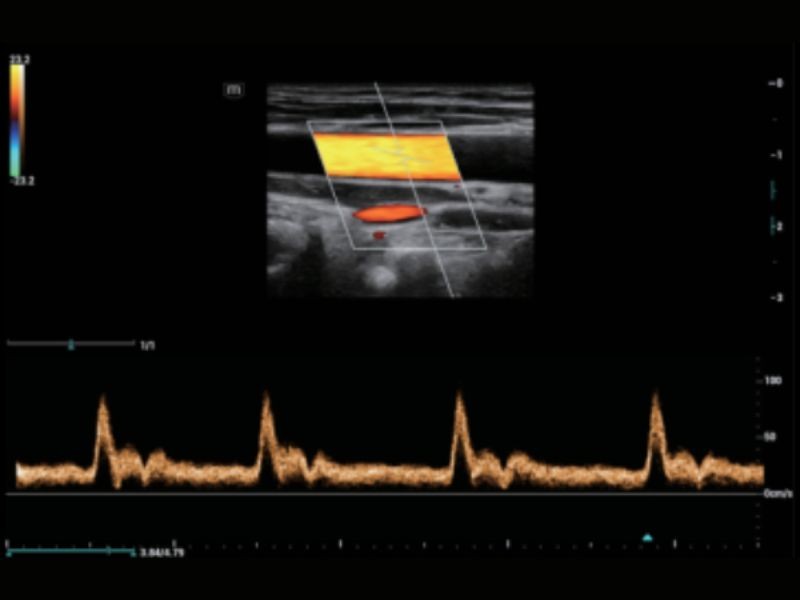

RIMT

Medição IMT em tempo real baseada em dados de RF

R-VQS

Coeficiente de dureza vascular e velocidade da onda de pulso (PWV)